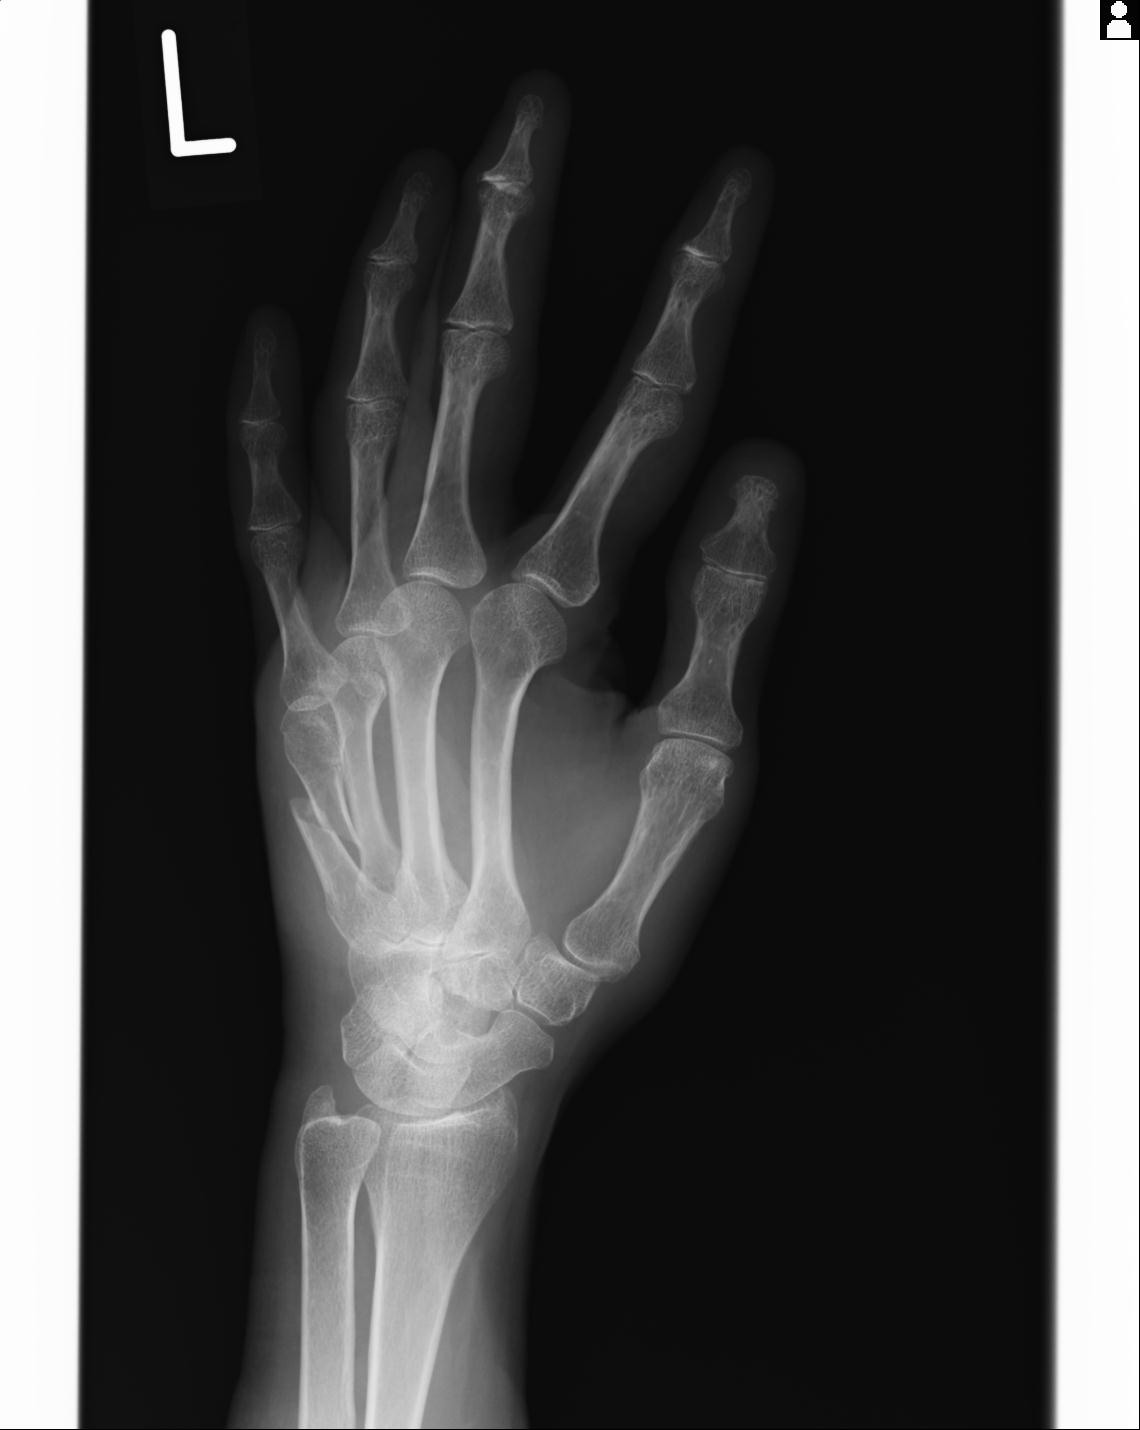

102766 1/5 1/12 左手関節 4R 28歳男性 左橈骨遠位端